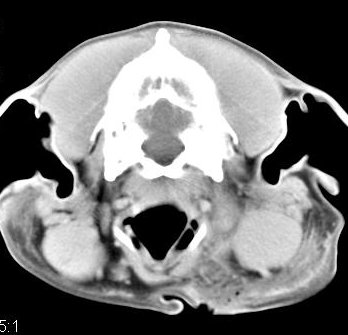

Diagnóstico neurológico | ||||||||||

imágenes de TC en el perro | ||||||||||

ejemplo de imágenes de TC en el perro. Nótese la celulitis en la región parotídea izquierda | ||||||||||